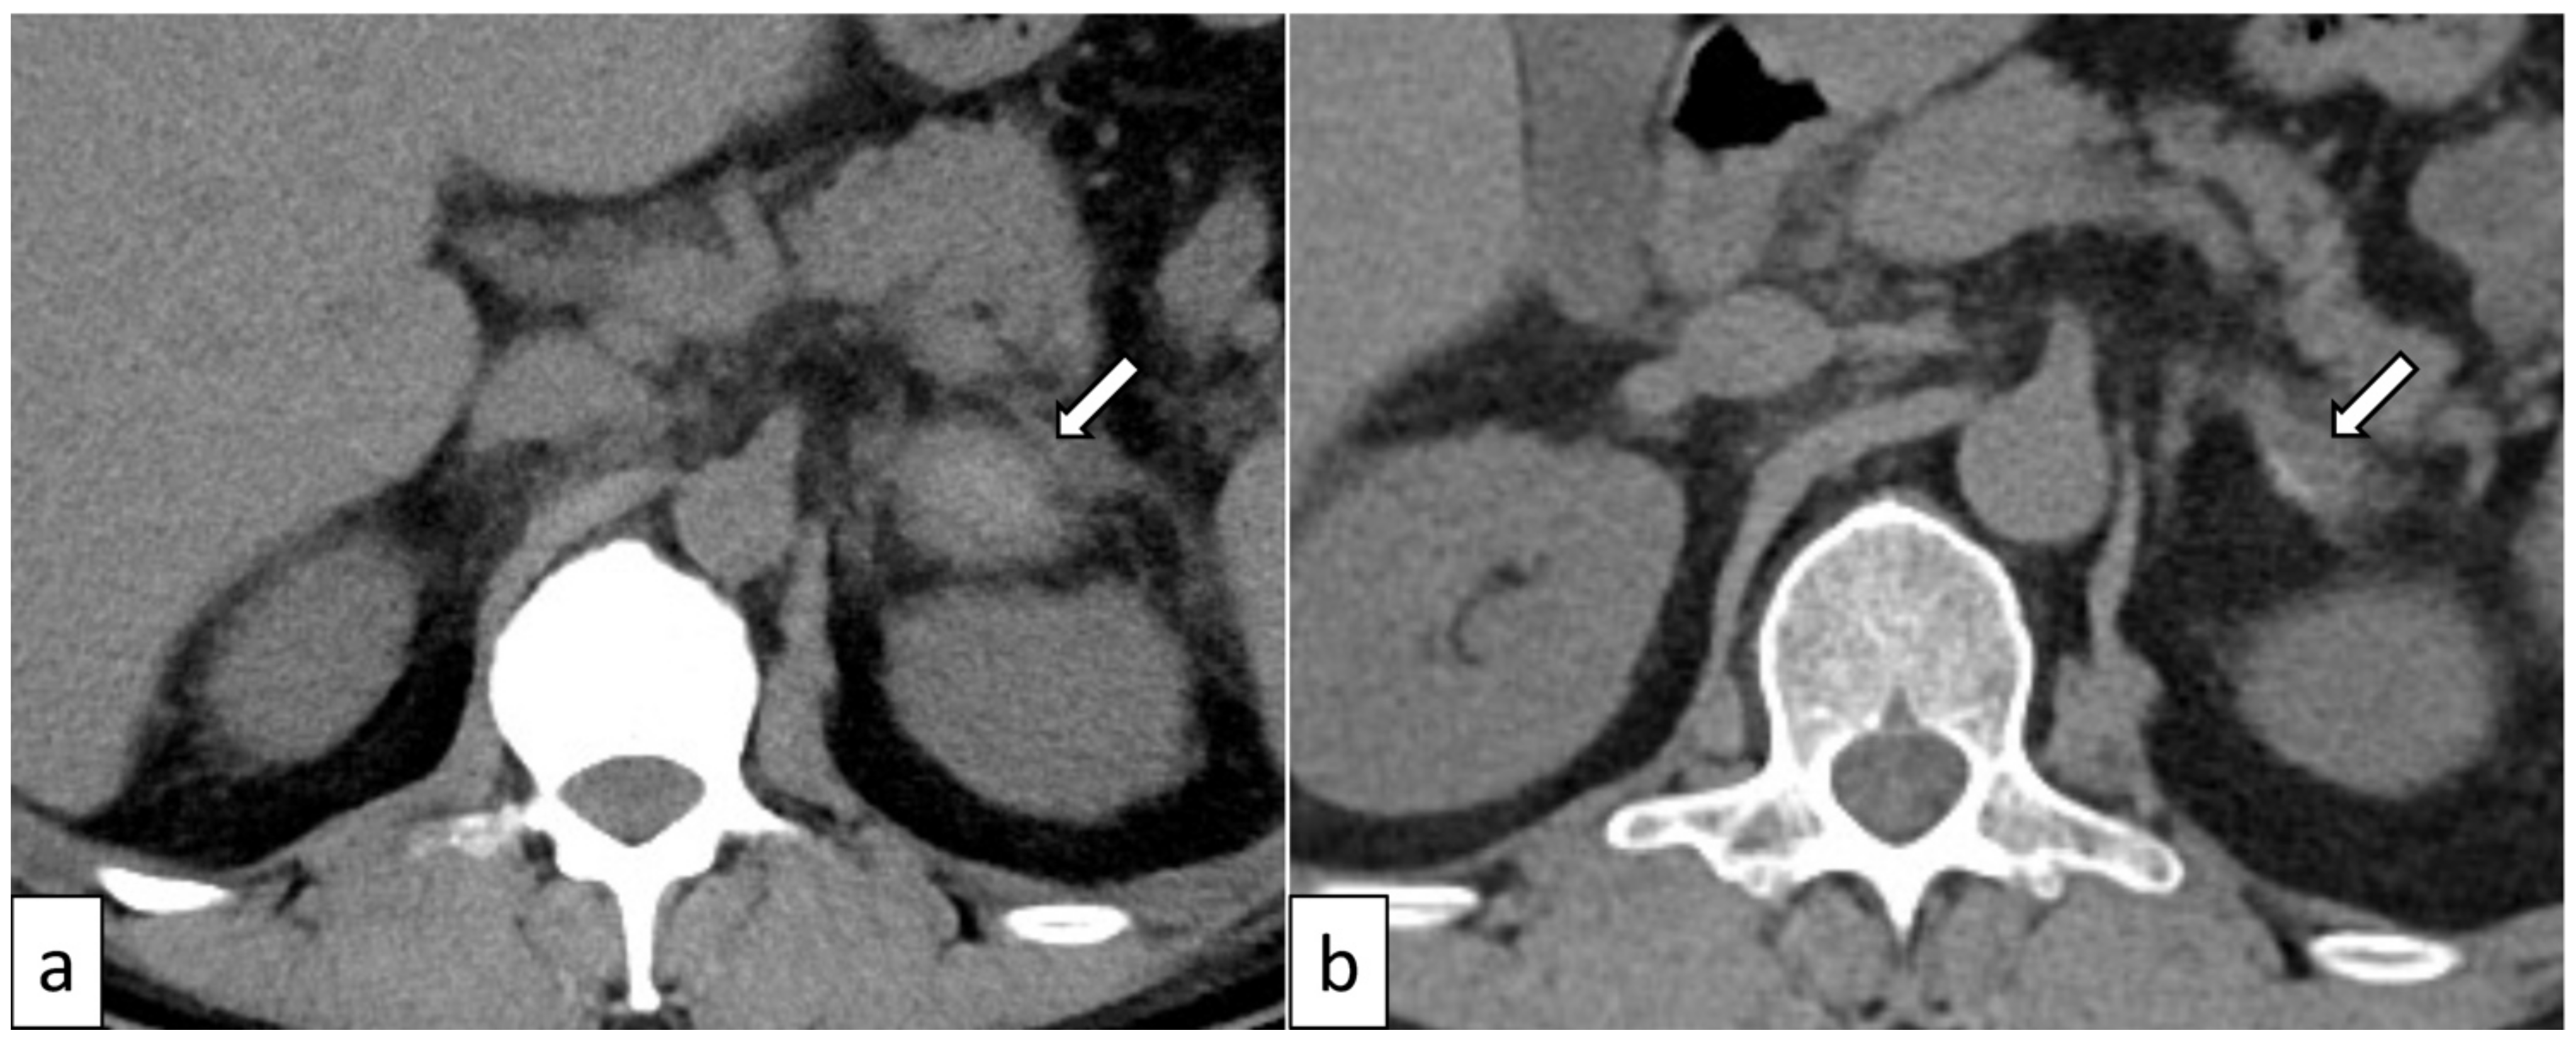

| Kano [15] | 50 (Figure 3) | Male | NO | Hemorrhage and contralateral adrenomegaly * | Bilateral | YES | YES | YES | YES |

3.5. Adrenal Hemorrhage